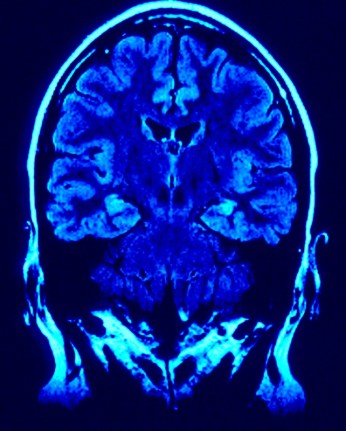

Når vi ser små babyer bevege seg langsomt, omstendelig og målbevisst er vi vitne til en omhyggelig opptrening av koordinasjon og motor mønstre som senere skal danne grunnlaget for alle bevegelsene som følger gjennom et langt liv. Det fokuset som barn i denne fasen har når de beveger seg er dypt konsentrert og vi kan fortrylles av hvor “søtt” denne konsentrasjonen rundt handlinger som å kneppe en knapp eller gripe rundt en gjenstand er. Men det som foregår i hjernen under en slik opptreninger er i virkeligheten noe som snarere burde påkalle vår beundring: Skanninger av hjernen til Ian når han utfører sine bevisst koordinerte bevegelser påviser en aktivitet i deler av hjernen som vanligvis kun brukes ved den mest sofistikerte form for intens konsentrasjon, områder som reserveres for handlinger som sjonglering.